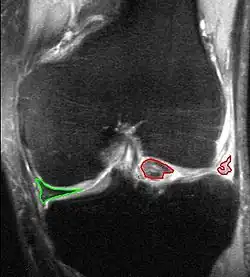

Korbhenkelriss, Ansicht von vorne; große Anteile des Außenmeniskus (rot) sind nach innen in das Gelenk verlagert, Innenmeniskus (grün) noch intakt